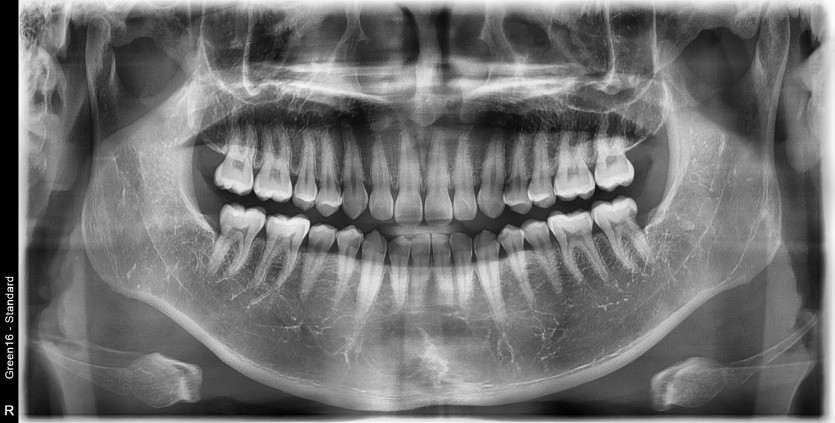

#28,38 사랑니 발치

구강 외과 전문의가 당일 발치했습니다.